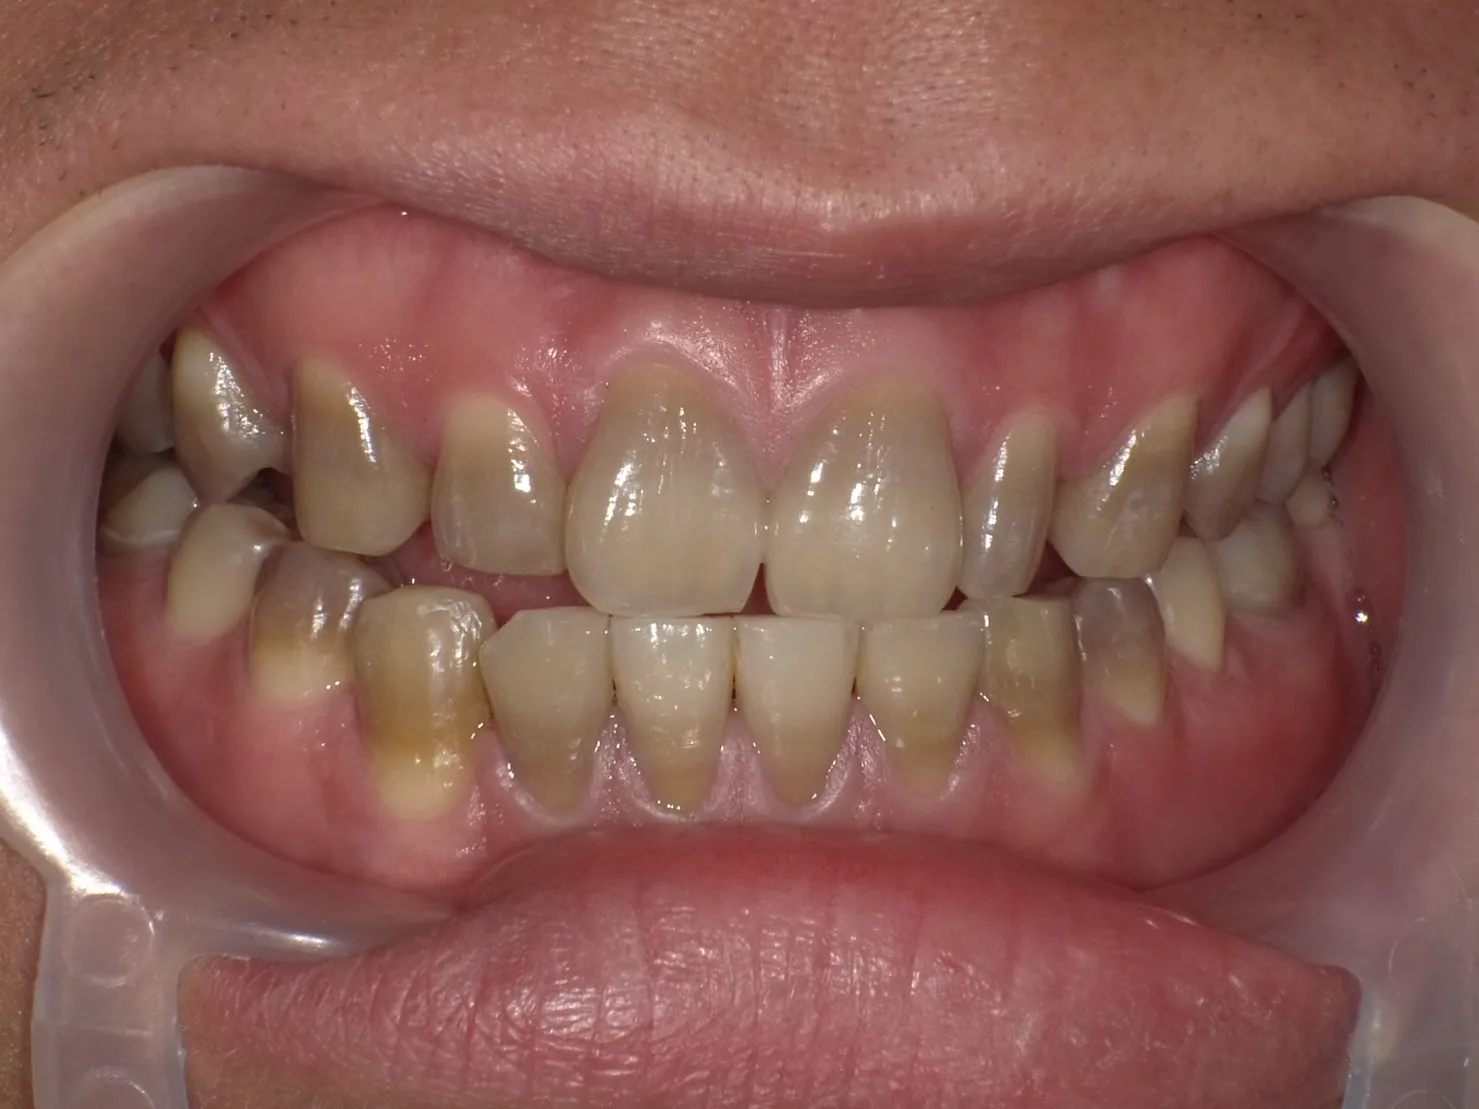

テトラサイクリン歯の治療法

テトラサイクリン歯の治療には、以下の方法が一般的に用いられます。

ホワイトニングは歯を削らないため、削らずに白くしてみたいという方に最適な治療法です。

特に、オフィスホワイトニングとホームホワイトニングを併用する

「デュアルホワイトニング」が効果的です。